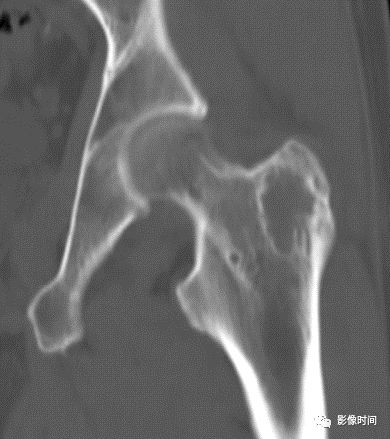

图 3  地图样破坏:骨内脂肪瘤

图 4 地图样破坏:骨转移瘤